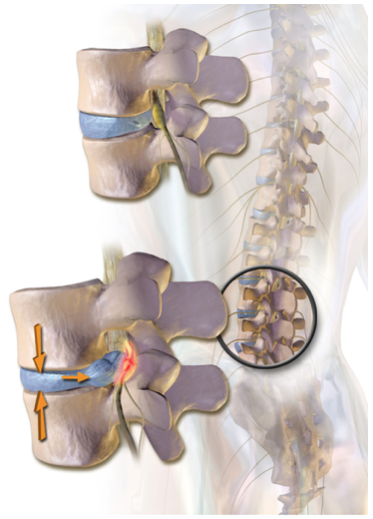

These injuries can occur with extreme compressive, forward-bending, and rotating forces such as car accidents. The disc is a structure in the spine which helps with shock absorption and mobility through the back. When a disc herniation occurs, the inner content (nucleus pulposus) of the disc will move outwards from the more solid outer layer (annulus fibrosus) (image 1). In more severe injuries, the inner content can compress on structures such as the spinal cord (image 2). Some symptoms experienced for this issue include pain traveling down the leg, difficulty bending down and back pain.

Image 2. Visual representation of a herniated lumbar disc. Source.